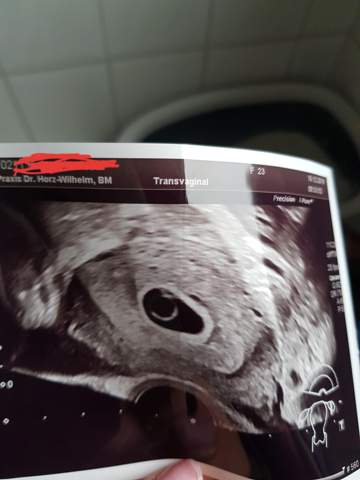

Definition einer Fehlgeburt Bei einer Fehlgeburt handelt es sich um den Verlust einer Schwangerschaft ab dem Zeitpunkt der Konzeption (Befruchtung) bis zur vollendeten 24 SSW (Schwangerschaftswoche) und einem Gewicht des Fetus kleiner als 500g Bis zur 12 SSW bezeichnet man eine Fehlgeburt als Frühabort, danach als Spätabort. 7 SSW Entwicklung des Babys Von außen sind noch keine Anzeichen zu erkennen (Sebastian Kaulitzki / Fotoliacom) In der 7 Schwangerschaftswoche ist der Embryo 5–8 mm groß und wiegt in etwa ein Gramm Die Fruchthöhle ist mit einer Größe von 25 mm schon eindeutig zu sehen Der Kopf wächst in diesen en besonders schnell. SSW 7 Sie sind nun 7 Wochen und eine bestimmte Anzahl von en schwanger!.

Fehlgeburt in der 7 SSW Hallo ihr Lieben, leider hatte ich letzte Woche in der 7 Woche eine Fehlgeburt Ich bin unendlich traurig und kann es immer noch nicht so ganz verstehen Und das blöde ist jetzt, ich darf bis Ende Februar nicht schwanger werden, weil mir die Windpocken Impfung fehlt BabyCente Fehlgeburt in der 7 SSW 17. Bei den „klinischen Schwangerschaften“ sind die FehlgeburtsRaten deutlich geringer Es gibt in den Studien etwas unterschiedliche Angaben, aber auch hier ist das Schwangerschaftsalter entscheidend für die Häufigkeit einer Fehlgeburt Nach einer australischen Studie liegt das Risiko in der 7 SSW bei 9,4 %, in der 8. Herzlich Willkommen in der netdoktorCommunity!.